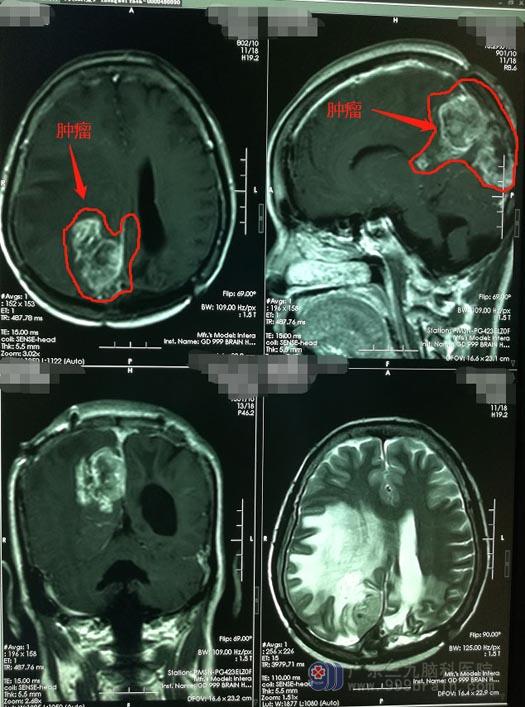

立即予胸部CT检查、咽拭子测试、血常规检查等,经过一项项严格的筛查,排除了新冠肺炎,收住神经外五科。头颅影像检查后,主管医生告诉钟姨的家人:脑膜瘤又复发了。

绝大多数脑膜瘤患者,手术治疗会获得较好的疗效,但是也有部分患者会有复发。脑膜瘤的复发与肿瘤的形状、位置及肿瘤的切除程度、病理类型和病理分级有关,如果肿瘤生长在重要的神经、血管旁,或与神经,血管粘连紧密时,手术难以全部切除,残留的部分就可能引起脑膜瘤复发。

第三次手术,对手术医生的技术要求很高,医院副院长、神经外五科主任鲁明带领团队,凭着扎实的手术功底及多年的成功经验决定迎着困难上,在全麻下为钟姨行右顶枕镰窦复发脑膜瘤切除术。术中见上失状窦顶枕部闭塞,肿瘤起源于顶枕部大脑镰,主体位于右顶枕部,小部分肿瘤自大脑镰突入左侧枕部,肿瘤深部长入右侧脑室角,部分肿瘤侵入脑实质,右侧脑室角破损,予以修补、肿瘤全部切除;顶枕部受肿瘤侵袭的部分大脑镰以及长入上失状窦内的肿瘤也予以切除,闭塞的上失状窦前后段均予以妥善结扎。手术过程顺利,术中无重要血管及主要静脉窦损伤。